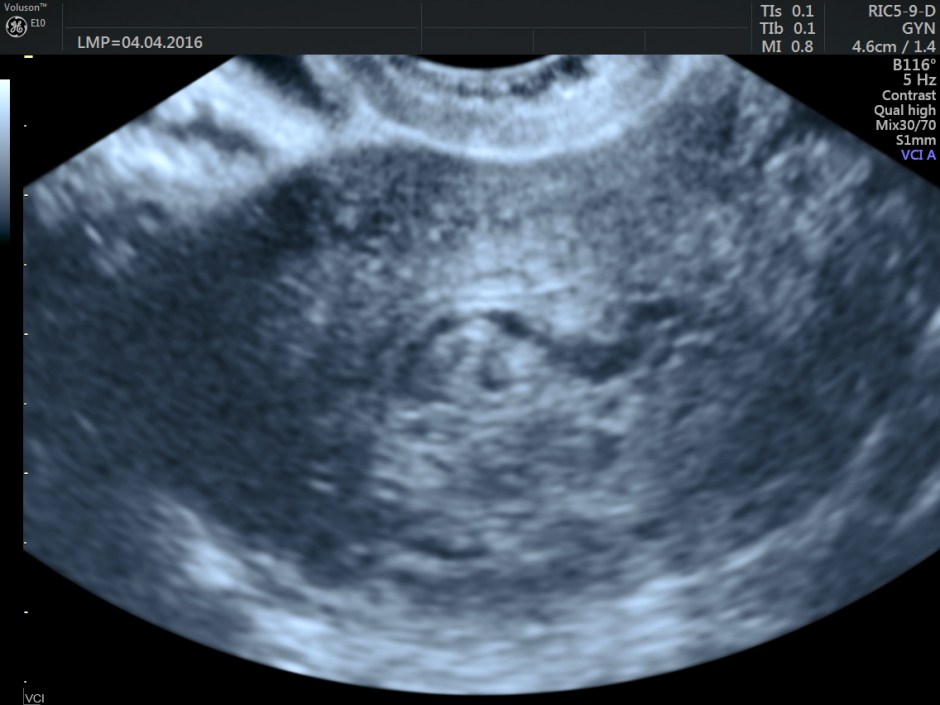

Volume contrast imaging pictures are given below:

Endometrium shows ? polypoid appearance; Irregular hypoechoic myometrial texture with some serpiginous appearance is seen.